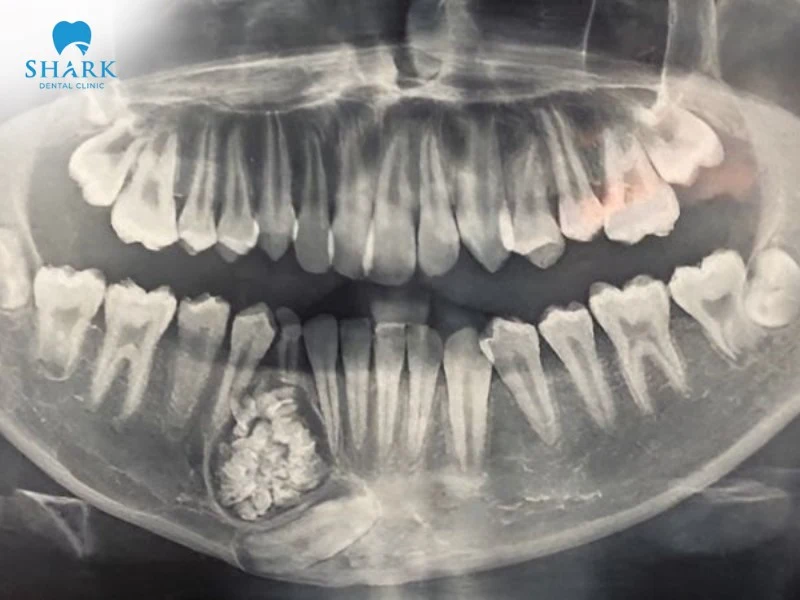

Nang thường được phát hiện tình cờ khi chụp X-quang (phim toàn cảnh Panorama hoặc phim quanh chóp) để kiểm tra các vấn đề răng miệng khác.

Tiêu xương hàm: Nang phát triển ngày càng lớn sẽ tạo ra áp lực, làm tiêu biến xương hàm xung quanh, khiến xương trở nên giòn và dễ gãy. Bạn nên tìm hiểu hình ảnh tiêu xương ổ răng để nhận biết mức độ tổn thương và điều trị kịp thời.